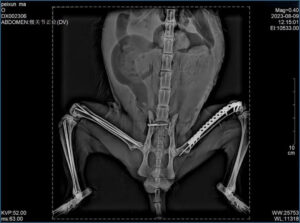

Once stabilized, attention turns to the limb. X-rays—taken from multiple angles—reveal a simple, closed, oblique fracture of the tibial shaft, with a similar fracture of the fibula. A CT scan may also be performed if available.

The surgeon exposes the tibia by carefully separating skin and muscle. A properly sized bone plate is selected, contoured to fit the bone, and positioned across the fracture. Screw holes are drilled, and screws—including a lag screw—are placed to secure the bone fragments. The fibula, being non–weight-bearing, is left to heal naturally.

Muscles and skin are sutured, and postoperative X-rays confirm correct implant placement.